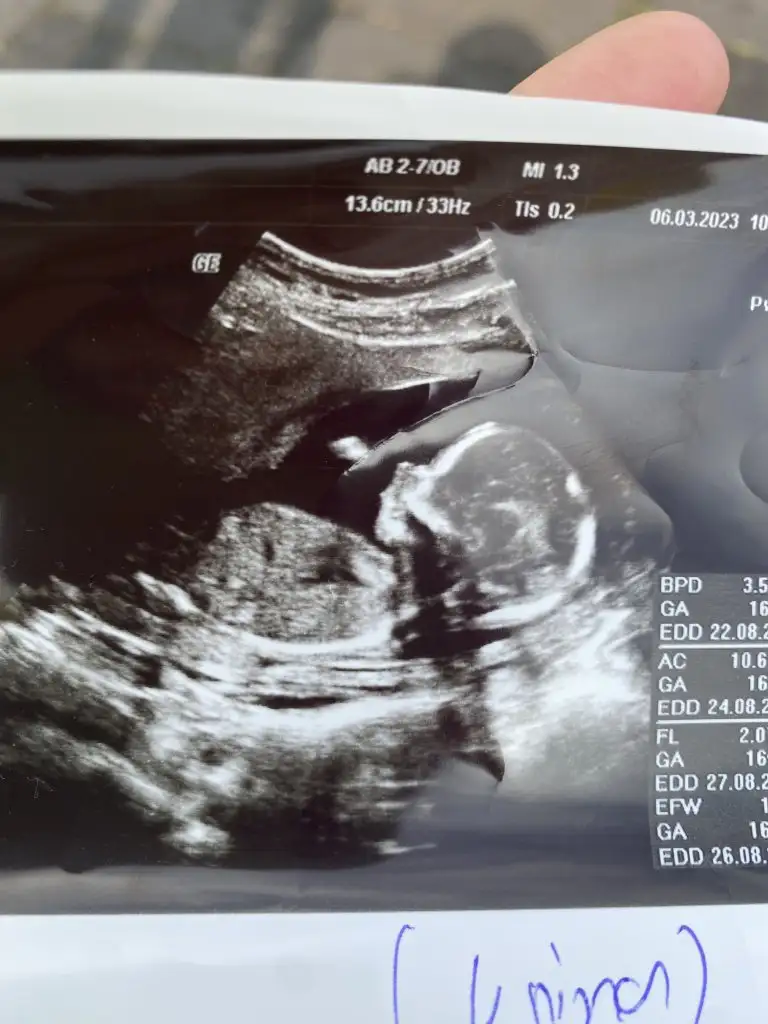

Pekiii bende ne dersin ?

Üstteki 9 haftalik diger ikisi 7 haftalik, ve vaginal ultrason :)